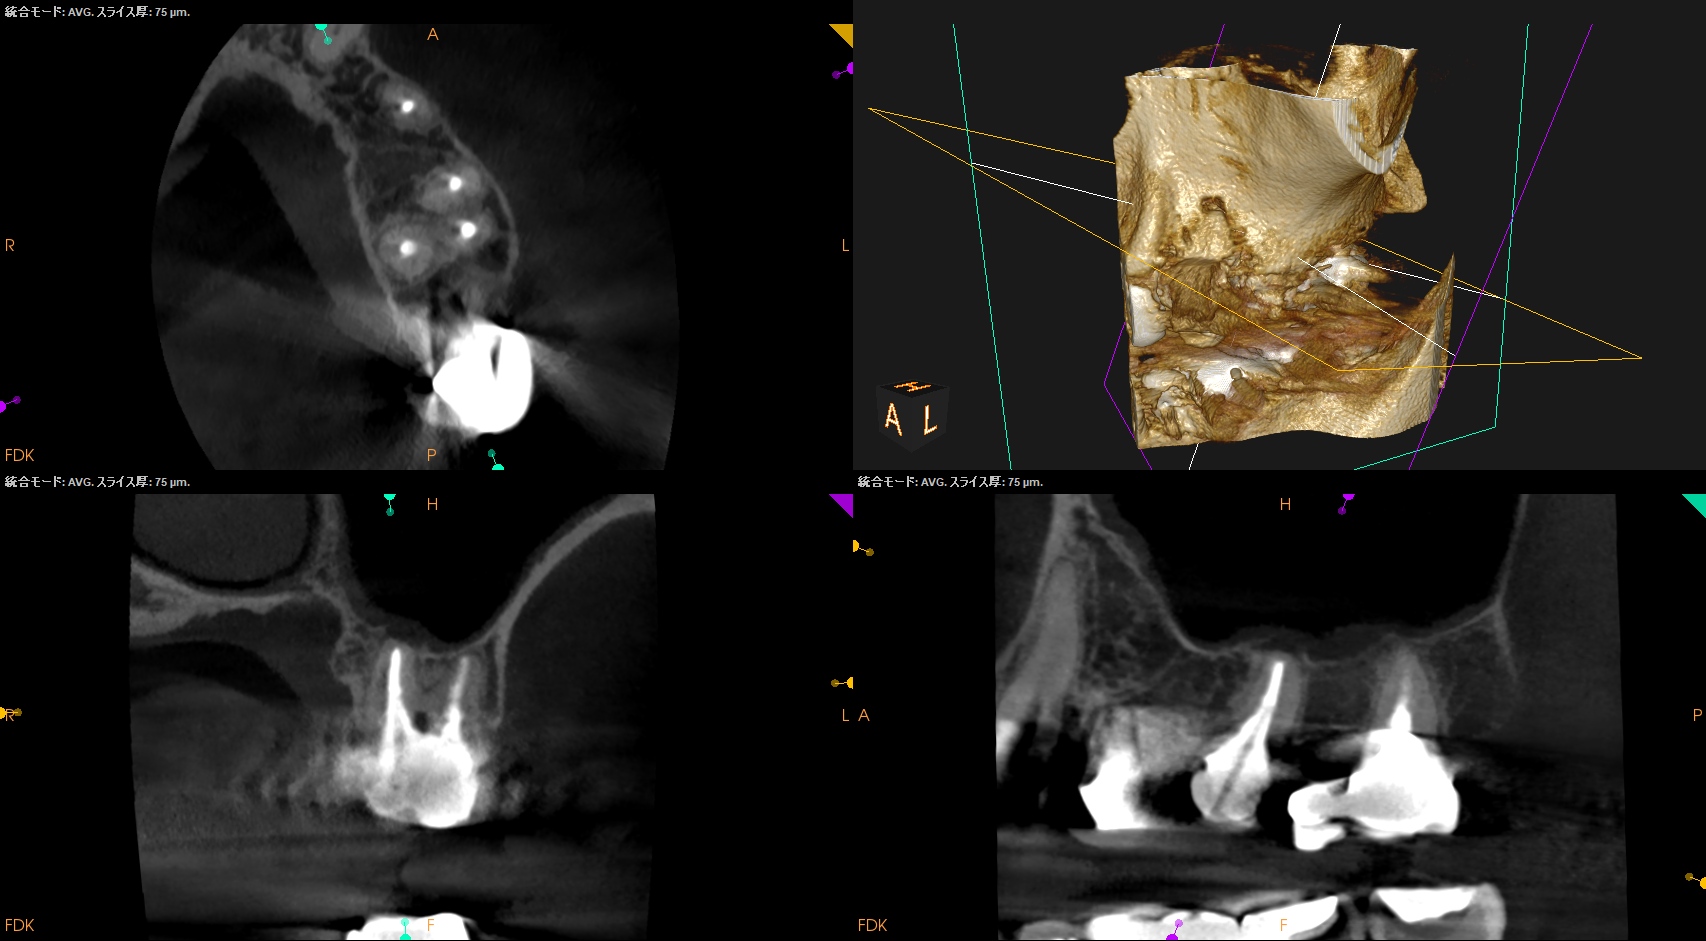

#3,14,16 Re-RCT 1yr recall(2025.10.20)

#3

MB

DB

P

#14

#16

初診時+治療直後と比較した。

劇的に病気が治癒している。

特に#16は凄まじい。

超音波洗浄しかできなかったのに根尖病変が治癒しているのだ。

免疫力が非常に強い患者さんなのだろう。